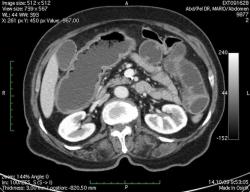

КТ брюшной полости. Женщина 73 года с жалобами на запоры.

Пациентка женщина 73 года. Предъявляет жалобы на запоры, спастические боли в брюшной полости.

ИзображениеЦиркулярное сужение в поперечной ободочной кишке. Ни это ли причина проблемм?

Новообразование в среднем отделе поперечной ободочной кишки с циркулярным сужением просвета и хронической механической толстокишечной непроходимостью. Признаков метастазирования в данной анатомической области не обнаружено. Пациент безусловно нуждается в хирургическом лечении.

Я не занимаюсь КТ, но сам характер сужения толстой кишки как-то вызывает сомнения, ракового ли он характера? Сужение то циркулярное, но больно уж ровненькое и нет признаков инфильтрации вокруг (хотя рак, конечно может иметь и такой вид). Ну, думаю dr.Mario со временем откроет карты и будет дана гистология.

Циркулярная стенозирующая опухоль (аденокарцнома) толстого кишечника; с типичной КТ презентацией и признаками обструкции. Пациентка была оперирована на второй день после КТ.